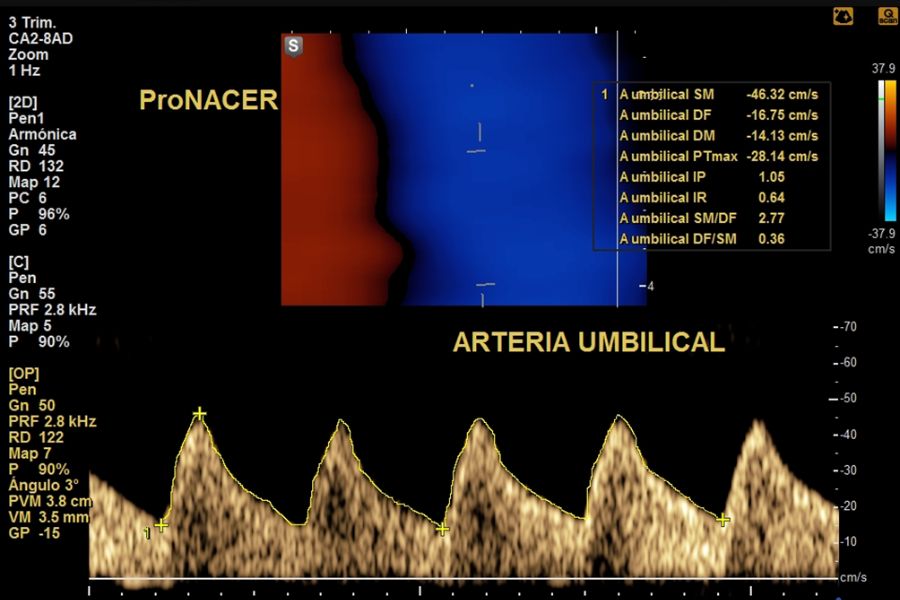

Doppler fetoplacentario